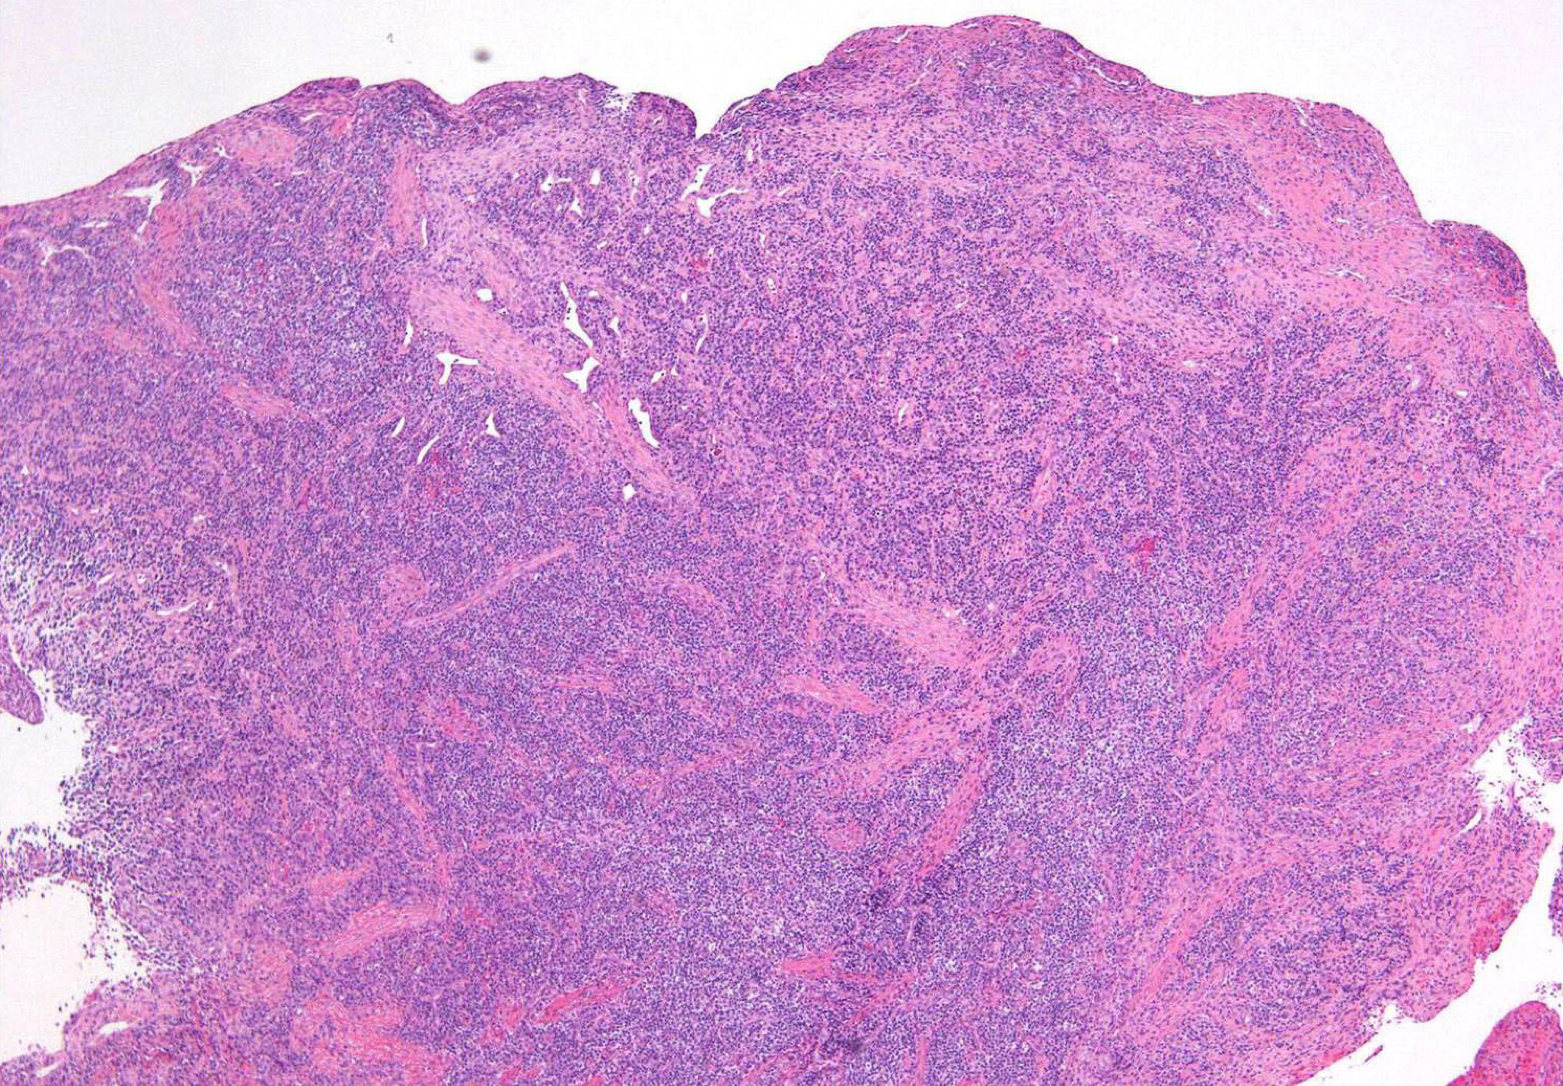

which potential result of periapical inflammation?

histopathological features:Â

granulation tissue surrounded by fibrous CT

tissue from apex of non-vital tooth socket

lymphocytic infiltrate may be intermixed w neutrophils, plasma cells, histiocytes, and occasionally mast cells or eosinophils Â

periapical granuloma